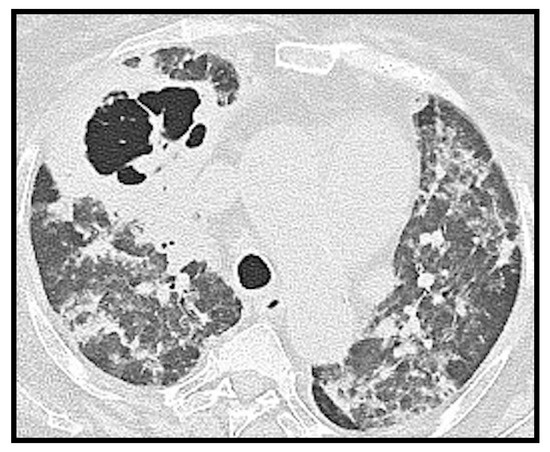

3.5. Pneumothorax and Pneumomediastinum

Spontaneous pneumothorax and pneumomediastinum (Figure 10) are also very infrequent findings in pediatric COVID-19-related pneumonia: a study [27] reported pneumothorax in 2% of cases, and a few case reports in the literature have described these findings [33,34], usually in adolescents with severe disease.

Figure 10. (AC): A 14-year-old girl with spontaneous pneumothorax and pneumomediastinum, in association with extensive ground glass changes. In Figure 10C consolidation of the right lower lobe is noted.